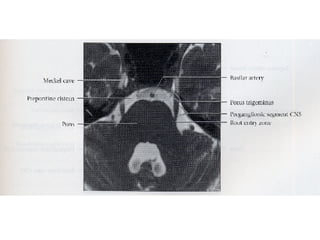

Nervos Cranianos Nervo trigêmeo- V Par 􀂄  Sensitivo 􀂄  Aferente somático geral 􀂄  Gânglio trigeminal - de Gasser 􀂄  N. oftalmico 􀂄  N. maxilar 􀂄  N. mandibular 􀂄  Exteroceptivo e Proprioceptivo

Nervos Cranianos Nervo trigêmeo- V Par 􀂄  Motor 􀂄  Eferente visceral especial 􀂄  M. temporal 􀂄  M. masséter 􀂄  M. pterigoideo lateral 􀂄  M. pterigoideo medial 􀂄  M. milo-hióideo 􀂄  M. digástrico-ventre anterior 1° arco branquial

Nervos Cranianos Nervotrigêmeo- V Par 􀂄 Sensitivo 􀂄 Aferente somático geral 􀂄 Gânglio trigeminal - de Gasser 􀂄 N. oftalmico 􀂄 N. maxilar 􀂄 N. mandibular 􀂄 Exteroceptivo e Proprioceptivo

Nervos Cranianos Nervotrigêmeo- V Par 􀂄 Motor 􀂄 Eferente visceral especial 􀂄 M. temporal 􀂄 M. masséter 􀂄 M. pterigoideo lateral 􀂄 M. pterigoideo medial 􀂄 M. milo-hióideo 􀂄 M. digástrico-ventre anterior 1° arco branquial